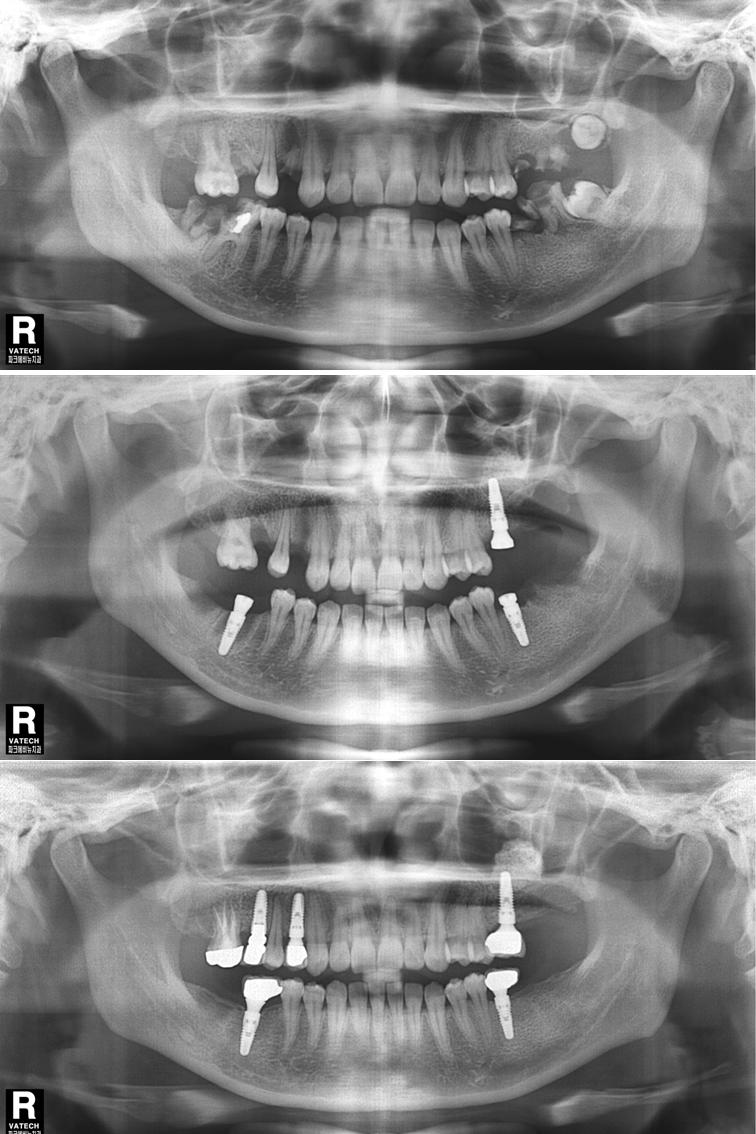

상악동거상술 이식술 뼈이식수술 치료전후 비교사진

상악동거상술